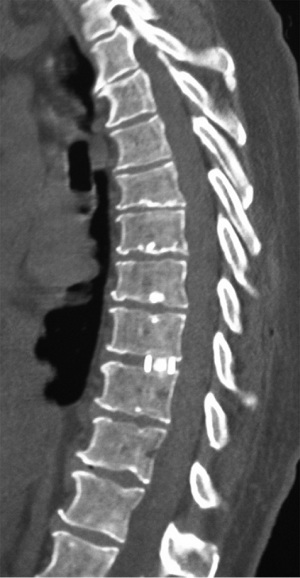

A 49-year-old male presented with a 4-day history of progressive myelopathy with bladder and bowel dysfunction, unsteadiness and leg numbness. He had no medical comorbidities and was a non-smoker. Examination demonstrated spastic gait, positive Romberg’s test, lower limb hyperreflexia with midthoracic sensory level and saddle anesthesia. Thoracolumbar MRI revealed an acute central T6-7 soft central disc prolapse compressing the spinal cord causing intrinsic high cord signal (Figure 1). MRI brain excluded mass lesion and demyelination. Two days of 16 mg dexamethasone treatment was provided without symptom response or improvement. Hence, the patient underwent a right transpleural T6-7 LIF. After complete channel discectomy, a ball tipped hook was used to remove the extruded central disc fragment through a rent in the ruptured posterior longitudinal ligament (PLL). The disc space was distracted with sequential interbody spacer trials until the appropriate height was achieved, followed by cage placement (6×16×35 mm3, 10 degree, CoRoent XL-T). Estimated blood loss (EBL) was less than 50 mL. A postoperative chest tube was not required for drainage. Postoperative chest radiography excluded pneumothorax and CT confirmed cord decompression and satisfactory prosthesis placement at T6-7. The patient exhibited rapid resolution of myelopathic symptoms and was discharged 5 days postoperatively. At 6 weeks postoperative the skin incision was well healed with excellent cosmesis (Figure 2) and he was no longer taking analgesic medication. The patient returned to light work duties at 8 weeks and then to full duties 3 months postoperatively. Solid fusion was confirmed on CT at 6-month follow-up (Figure 3). The patient reported a vast improvement in pain, from a visual analogue scale (VAS) of 10/10 preoperatively, to 1/10 at 24-month follow-up. There were also improvements in Oswestry Disability Index (ODI) (84 to 0), and SF-36 physical component score (PCS) (11 to 50) and mental component score (MCS) (54 to 55).